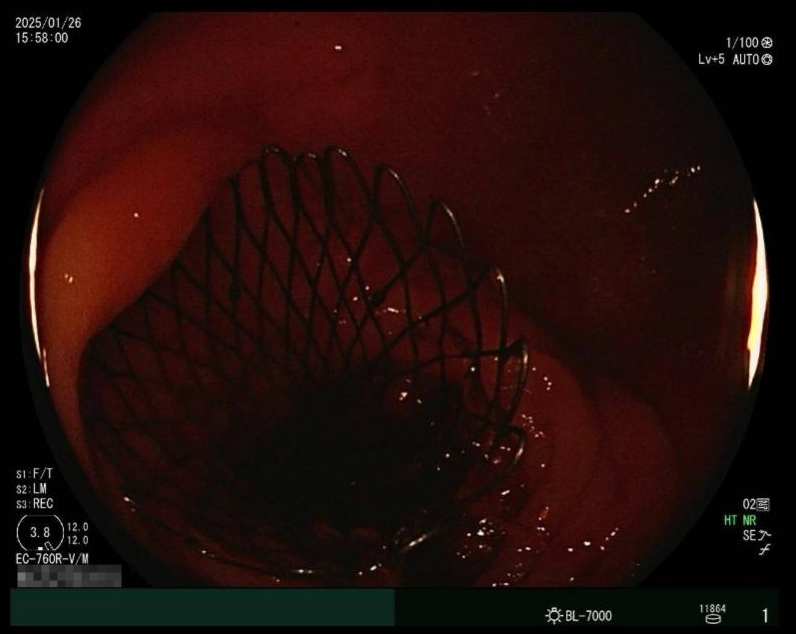

彼時正值除夕前夕,時間緊迫,王志斌主任迅速聯系北京中醫藥大學東方醫院方莊院區脾胃肝膽科王林恒主任,協調手術相關事宜。在兩個院區的緊密配合下,患者當日下午順利轉入方莊院區內鏡中心。在內鏡室,脾胃肝膽科團隊憑借過硬的專業技術和豐富的臨床經驗,有條不紊地進行操作,并順利完成并開啟生命綠色通道——腸道支架介入手術。

術后,患者的腹脹痛癥狀迅速得到緩解,很快恢復了排氣排便。第二天,患者就能正常進食米湯,飲食逐步向流食過渡。目前,患者病情平穩,已經轉入方莊院區外科接受后續治療。

治療前腹CT示腸腔明顯擴張 治療后立位腹平片示腸道梗阻較前明顯緩解